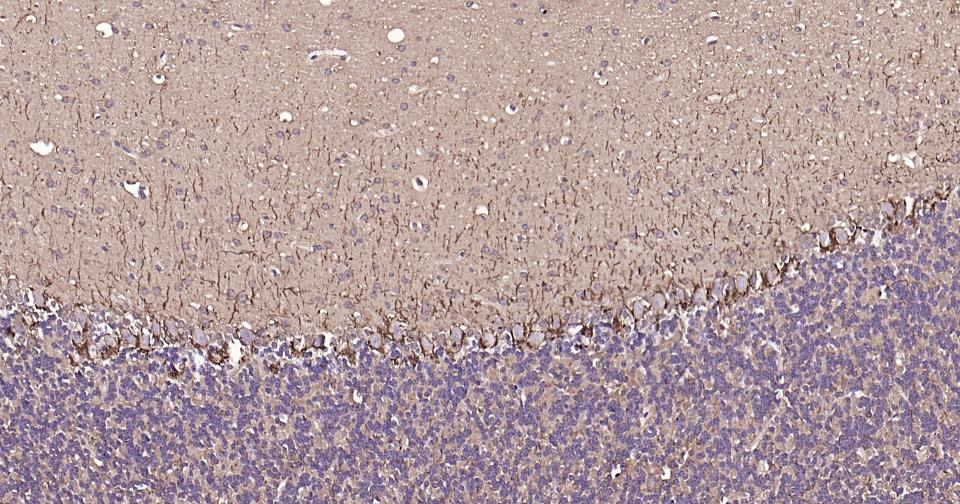

Paraformaldehyde-fixed, paraffin embedded Rat Cerebellum; Antigen retrieval by boiling in sodium citrate buffer (pH6.0) for 15 min; Antibody incubation with NEFH Monoclonal Antibody, Unconjugated(bsm-60885R) at 1:200 overnight at 4°C, followed by conjugation to the SP Kit (Rabbit, SP-0023) and DAB (C-0010) staining.